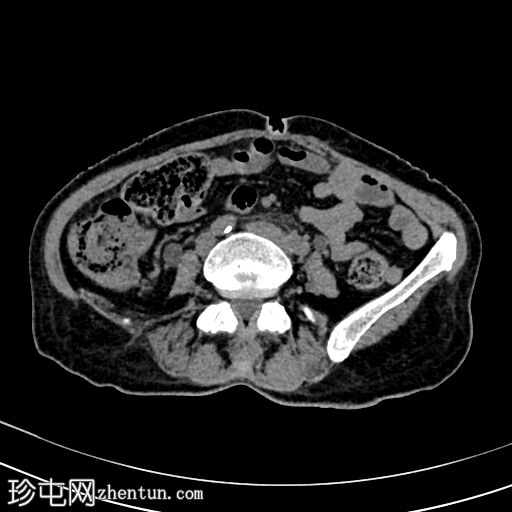

轴位增强(门静脉期)

2.jpg

可见膀胱壁不规则弥漫性明显增厚,伴壁内气体,符合气肿性膀胱炎的影像学表现。

可见双侧膀胱输尿管连接处闭塞,导致双侧肾盂输尿管积水。

右肾中度肾积水,肾实质厚度正常;左肾重度肾积水,肾实质厚度减少。

该患者存在双侧输尿管肾积水;然而,输尿管壁未见异常增厚,输尿管或肾集合系统内也未见气体灶(CT未检测到输尿管和肾实质感染的证据)。